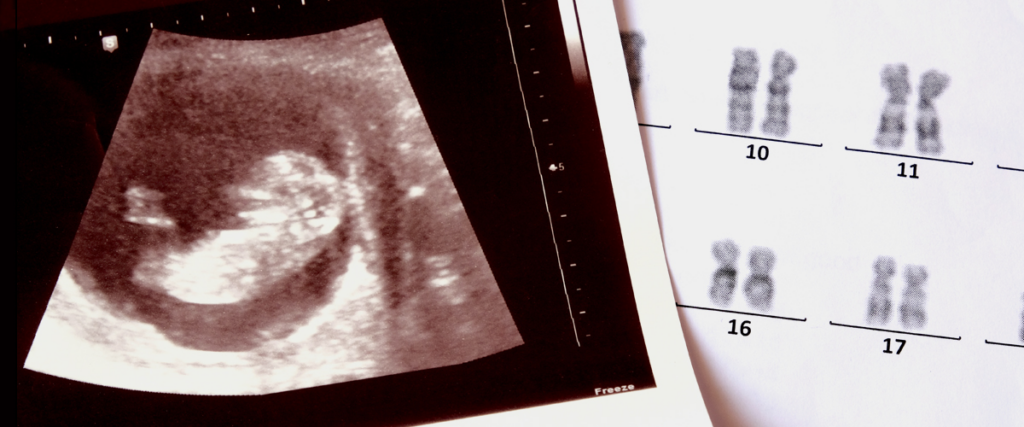

At his Clayton practice, Centre for Infertility Solutions, Dr Lolatgis is known for his investigation and treatment of immunological causes of recurrent miscarriage and implantation failure, including DQ alpha gene matches. He would treat an average of 2500 patients each year.

His popularity grew nationwide as he offered a rare treatment for women diagnosed with reproductive immune issues where their body effectively attacked an embryo.

The treatment, Lymphocyte Membrane Immunotherapy Treatment (LMIT), is an emerging, experimental fertility therapy to help the mother’s immune system tolerate the embryo rather than attack it.